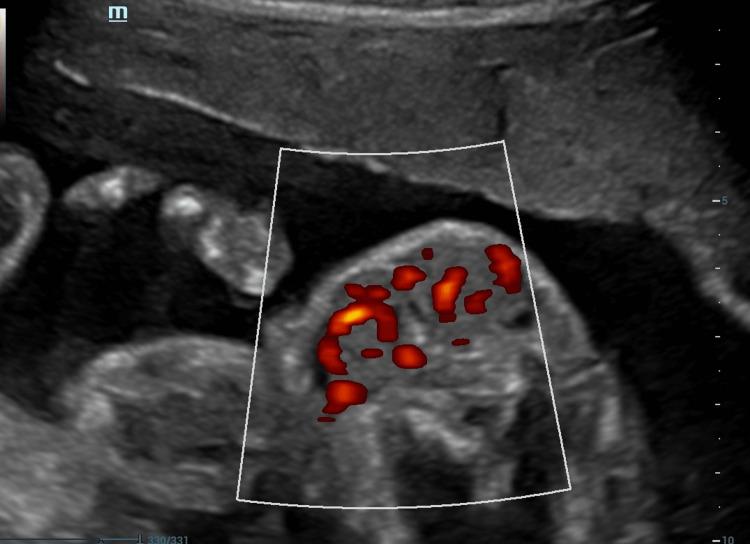

甲状腺功能正常的患者诊断出胎儿甲状腺肿:胎儿甲状腺疾病的一种罕见表现

Fetal Goiter Diagnosed in a Euthyroid Patient: An Unusual Presentation of the Fetal Thyroid Disease.

Fetal thyroid disease is rare, and the disease is mostly contextualized in the setting of a treated maternal thyroid disease. The presentation of thyroid disease in the fetus of a euthyroid mother is unusual. This paper presents the case of a 21-week pregnant woman with an incidental finding from a detailed anatomy ultrasound and evaluates available diagnostic and therapeutic management options. There is no consensus with sufficient evidence given the unusual presentation of this type of pathology. In most cases, the evidence is in the etiology of a mother with previous thyroid pathology that modifies the fetal outcome. Hence, it is important to describe cases to accumulate and, at some point, sufficient evidence of different treatments, with the intention of improving the quality of the recommendations. The management of fetal euthyroid goiter is a complex challenge. Most specialists manage the information on a case-by-case basis, with the same general goals as in patients with other thyroid pathologies.

摘要

胎儿甲状腺疾病较为罕见,且该疾病大多与已接受治疗的母体甲状腺疾病相关。甲状腺功能正常的母亲所怀胎儿出现甲状腺疾病的情况并不常见。本文介绍了一名21周孕妇的病例,该孕妇在详细的解剖超声检查中意外发现相关情况,并评估了现有的诊断和治疗管理方案。鉴于这类病理情况的不寻常表现,目前尚无足够证据支持的共识。在大多数情况下,证据存在于有既往甲状腺病理情况的母亲的病因中,这会改变胎儿的结局。因此,描述病例以积累不同治疗方法的充分证据很重要,目的是提高建议的质量。胎儿甲状腺功能正常的甲状腺肿的管理是一项复杂的挑战。大多数专家逐案处理信息,其总体目标与其他甲状腺疾病患者相同。